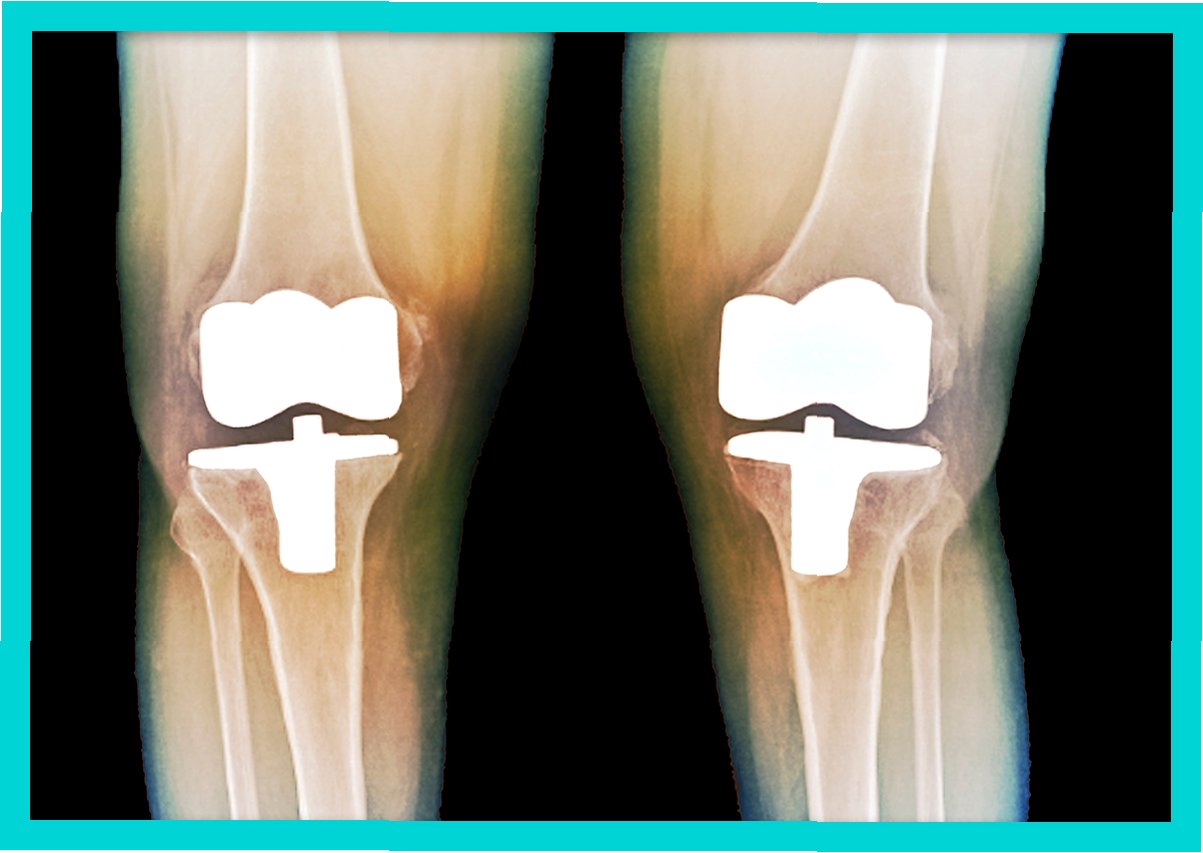

관절은 우리 몸의 움직임을 가능하게 하는 중요한 부분입니다. 하지만 관절 연골이 손상되거나 닳아 없어지면 극심한 통증과 함께 일상생활에 큰 불편함을 겪게 됩니다. 이러한 경우, 인공관절수술은 삶의 질을 향상시키는 효과적인 치료 방법이 될 수 있습니다. 인공관절수술은 손상된 관절을 인공관절로 대체하여 통증을 완화하고 관절의 기능을 회복시키는 것을 목표로 합니다. 수술 후에는 보다 자유롭고 활동적인 생활을 누릴 수 있으며, 긍정적인 심리적 변화도 기대할 수 있습니다. 인공관절수술은 단순히 통증을 없애는 것을 넘어, 환자가 건강하고 행복한 삶을 되찾도록 돕는 중요한 과정입니다.

인공관절수술은 일반적으로 손상된 관절 부위를 절개하고, 손상된 뼈와 연골을 제거한 후 인공관절을 삽입하는 방식으로 진행됩니다. 수술 시간은 관절 부위, 수술 방법, 환자의 상태에 따라 다르지만, 대개 1~3시간 정도 소요됩니다. 수술 후에는 통증 관리와 함께 조기 재활 운동을 시작하여 관절의 기능 회복을 돕습니다. 초기에는 보행 보조기구(목발, 보행기 등)를 사용하며, 점차적으로 사용 빈도를 줄여나갑니다. 재활 운동은 관절의 가동 범위를 늘리고 근력을 강화하여 일상생활 복귀를 돕는 데 매우 중요합니다. 회복 기간은 개인의 상태, 수술 방법, 재활 노력에 따라 다르지만, 일반적으로 수술 후 3~6개월 이내에 일상생활로의 복귀를 목표로 합니다. 꾸준한 재활과 관리를 통해 건강한 관절 기능을 회복하고 오랫동안 유지할 수 있습니다.